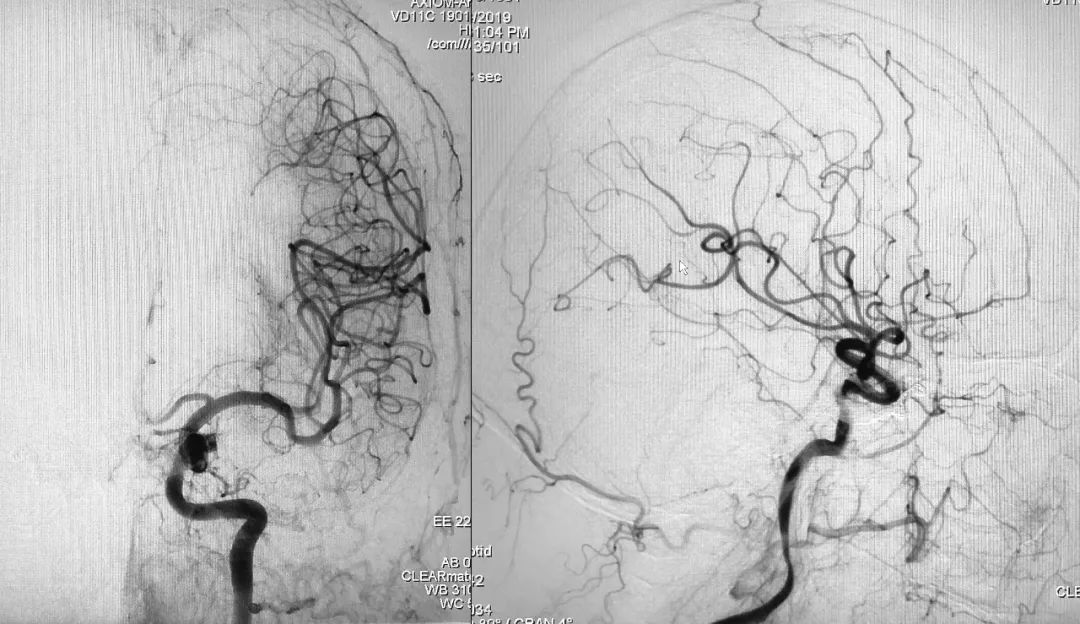

2018年10月12日行DSA示右侧海绵窦区硬脑膜动静脉瘘(Barrow D型),由双侧颈内、颈外动脉脑膜支供血,由右侧眼上静脉、岩下窦引流。

右侧颈总动脉正、侧位造影:

左侧颈总动脉正、侧位造影:

将造影管移入右侧颈总动脉,正、侧位造影显示瘘口不显影:

正、侧位蒙片显示Onyx-18胶在右侧海绵窦内的铸型(约4.5 mm):